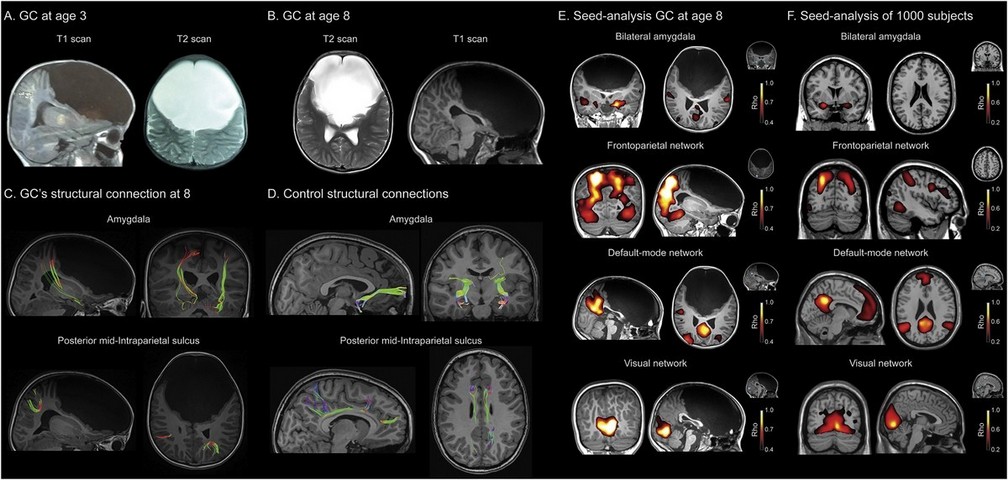

"Gabriela carece del lóbulo frontal, que es la parte más evolucionada que tiene el cerebro. Allí se determina el control de la conducta, el procesamiento de las emociones, los deseos, las llamadas ejecutivas de determinada acción, el lenguaje y otras más. Esa porción cerebral es realmente como una computadora compleja, donde se mantienen más conexiones. La niña presenta solamente un 10% de esa corteza prefrontal, pero al estudiarla vimos que no tiene ninguna conexión cerebral", sostuvo Ibañez.

Todas las teorías sobre la función cerebral coinciden en la gran complejidad de los lóbulos frontales y en su papel clave para funciones específicas, tales como la toma de decisiones, la conciencia, la memoria, el lenguaje y la cognición social. Es una región conectada a través de más de 12 vías con el resto del cerebro e incluye nodos críticos de muchas redes funcionales.

"Si bien las imágenes estructurales muestran la ausencia del lóbulo cerebral, la tractografía y conexiones de neuronas se reorganizaron de forma plástica desde su concepción en el seno materno y durante su niñez. También observamos que las conexiones funcionales, las redes por donde se transmiten las órdenes cerebrales se reorganizaron", aclaró el profesional.

"Eso significa que en condiciones de neurodesarrollo, el cerebro puede generar una plasticidad enorme al punto de desarrollarse casi normalmente. Fue una neuroadaptación del desarrollo cerebral increíble", precisó Ibañez.